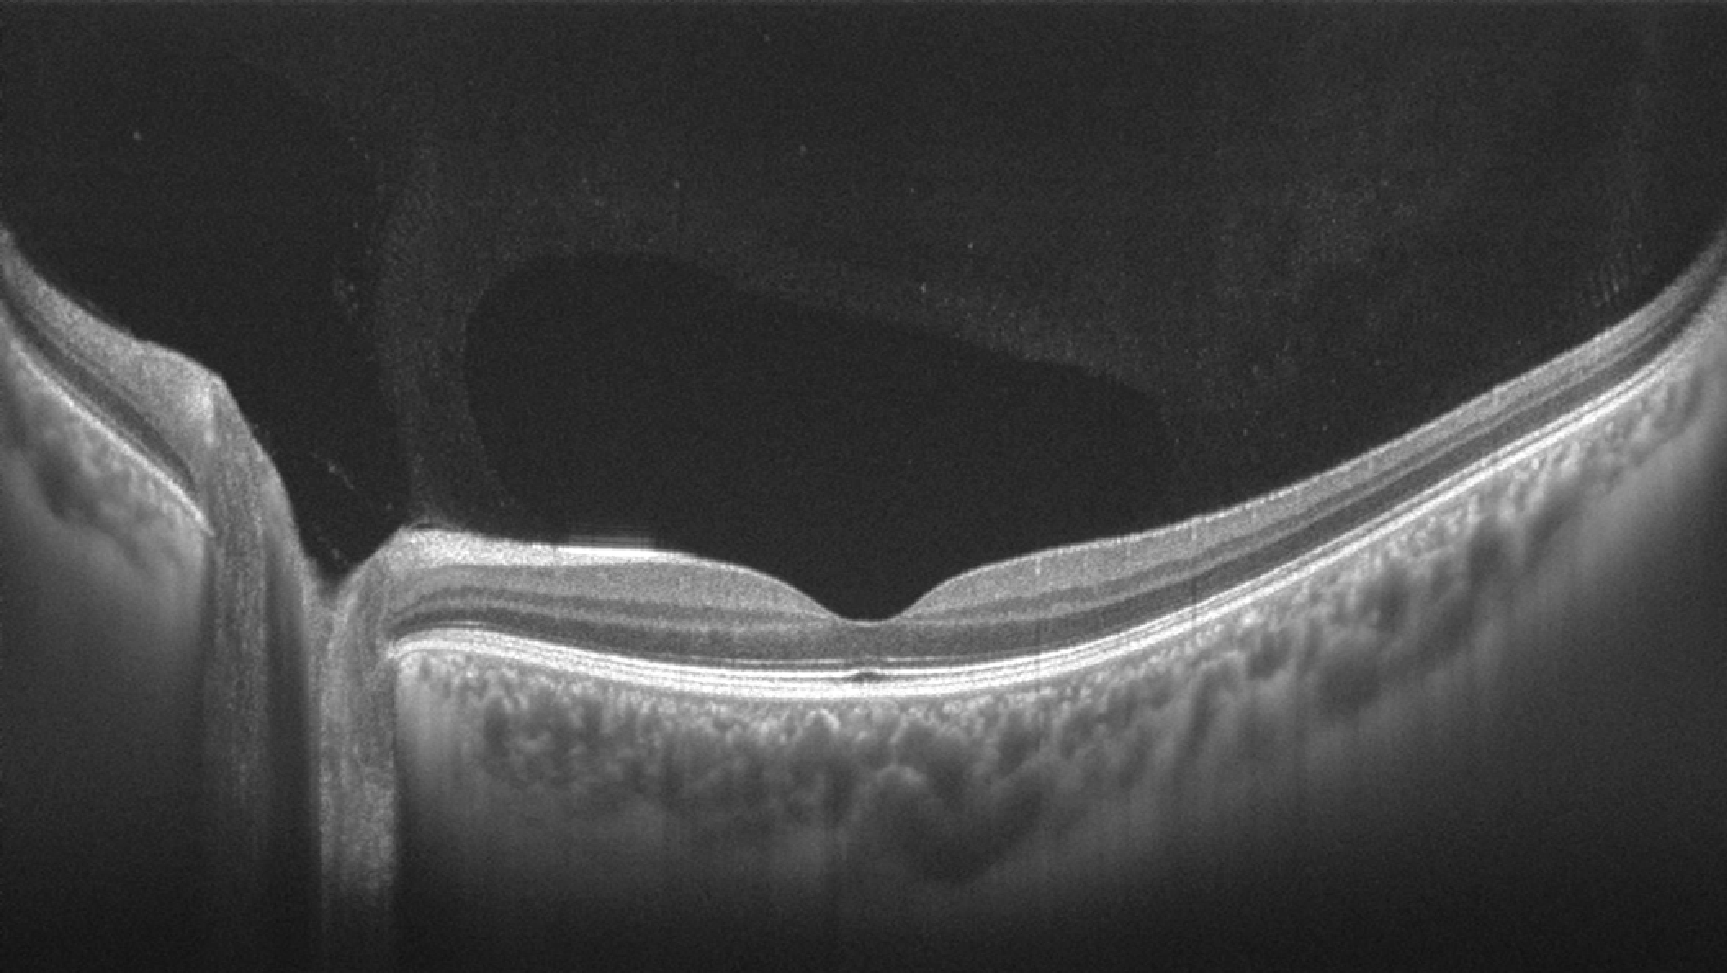

图2所示. a手术治疗前的黄斑裂孔的oct检查.